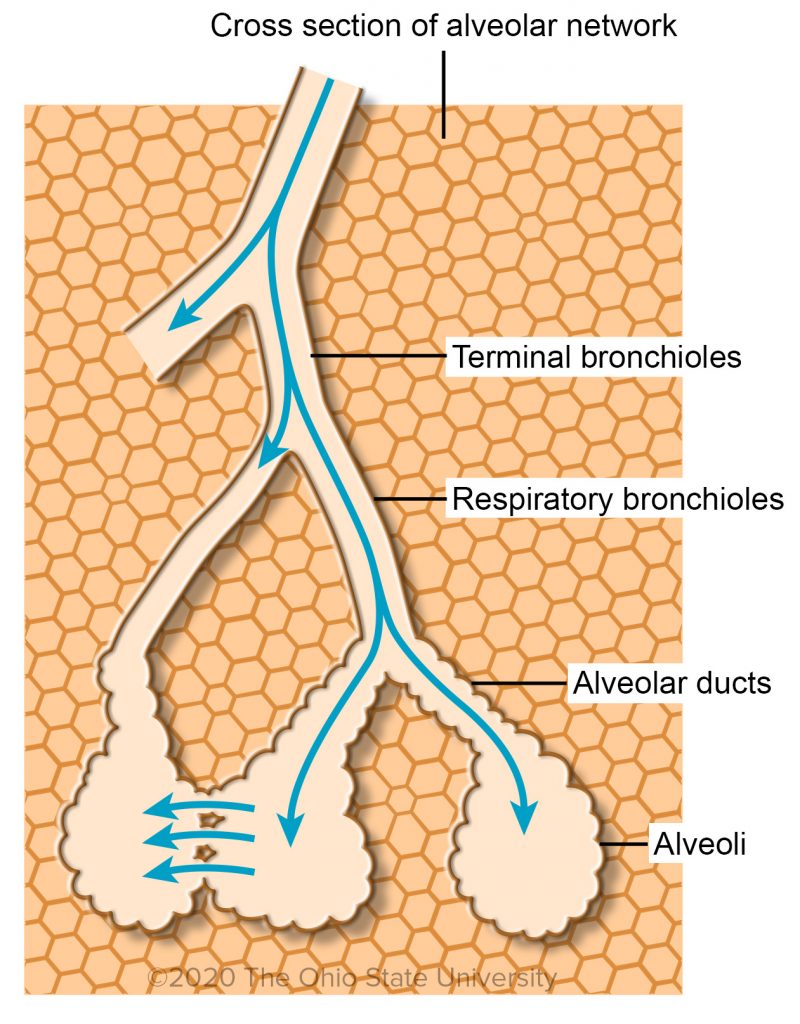

Air Conduction: Terminal Bronchioles, Respiratory Bronchioles And

ohiostate.pressbooks.pub

ohiostate.pressbooks.pub

bronchioles terminal respiratory alveolar ducts bronchiole alveoli histology conduction

Air Conduction: Terminal Bronchioles, Respiratory Bronchioles And

ohiostate.pressbooks.pub

ohiostate.pressbooks.pub

bronchioles terminal respiratory alveolar ducts bronchiole alveoli histology conduction ohiostate pressbooks